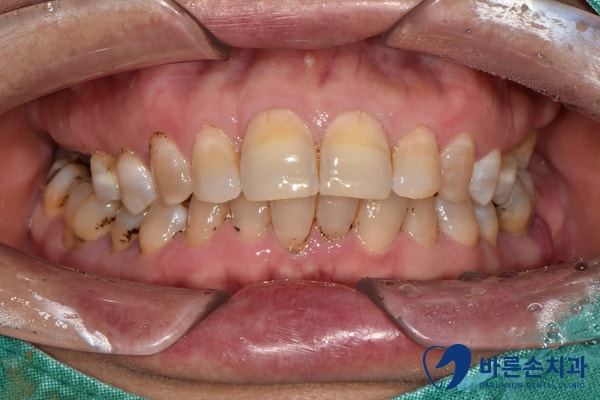

상하악 어금니 발치가 필요한 상태의 치료 전 모습, 23.11.30

초진 사진 입니다.

어금니가 대부분 부러져서 뿌리가 남아 있거나, 치주염으로 인해 흔들리는 상황 입니다.ㅠㅠ

치은연하(잇몸 밑으로 내려간) 치석으로 인해 치주염이 심합니다.